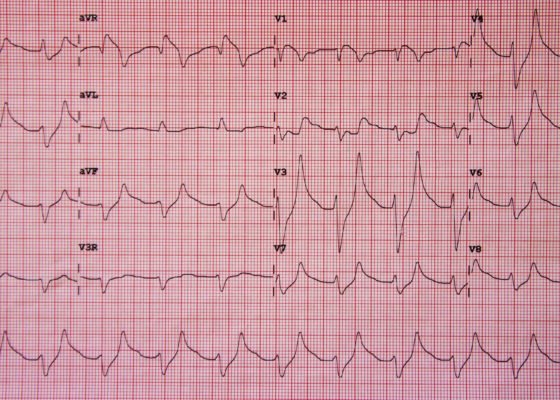

Hyperkalemia on ECG

DOI: https://doi.org/10.21980/J8K017Initial ECG shows tall, peaked T waves, most prominently in V3 and V4, as well as QRS widening. These findings are consistent with hyperkalemia, which was promptly treated. Follow-up ECG post-treatment shows narrowing of the QRS complexes and normalization of peaked T waves.